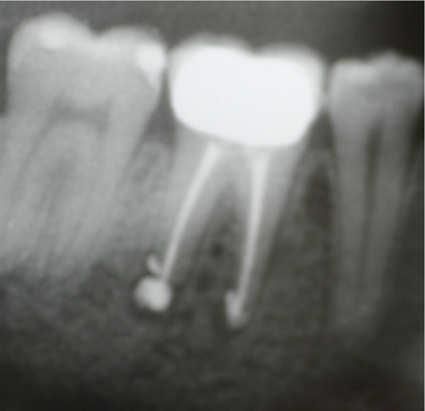

Decontamination and Biostimolation with an diode Laser 810nm